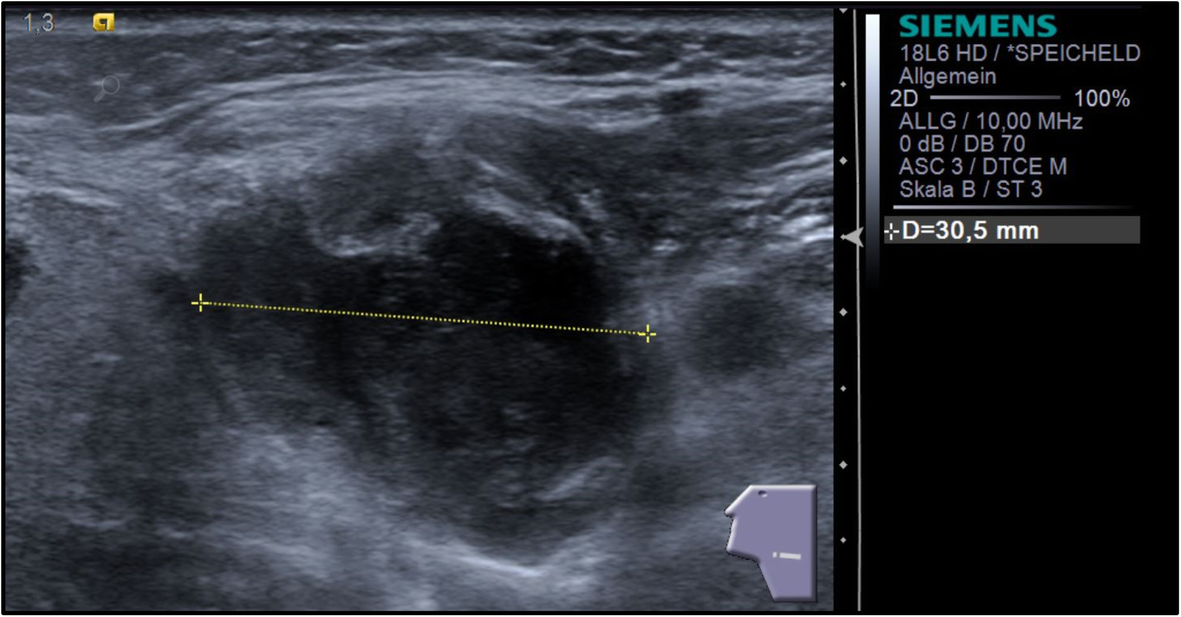

Figure 1 from Lymph node abscess due to Actinomyces viscosus in a cat